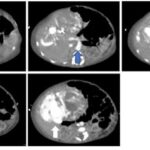

En las lesiones hipervasculares que reportamos se incluye al CHC, al hemangioma y a la HNF que fueron mejor caracterizadas en la fase arterial del estudio dinámico por TCMD. se analizaron a las lesiones hepáticas por su forma de realce en la fase arterial y reportaron un valor predictivo positivo de 82% y una especificidad de 80% en los hemangiomas, metástasis y CHC. Otros datos asociados al CHC (Anexos 8 y 9-A)(20) fueron la hepatopatía previa, fístula arterioportal y trombosis de la vena, los cuales demuestran la asociación de los CHC con fístula arterioportal, y en el seguimiento de diferentes pacientes se encontró que no necesariamente la presencia de una fístula arterioportal se asocia con tumor maligno, ya que se ha encontrado asociaciones con hemangiomas. La mayoría de las lesiones hipovasculares que se encontraron corresponden a quistes hepáticos simples. Las lesiones seudotumorales fueron representadas por los abscesos hepáticos que fueron drenados y, en segundo lugar, la infiltración grasa.

El principal factor de riesgo para su desarrollo es la cirrosis, principalmente la relacionada con la hepatitis viral crónica. Es este caso la hepatitis C, cirrosis alcohólica, cirrosis causada por hemocromatosis y cirrosis biliar primaria. La mayor parte de los casos en esta zona están relacionados con el virus de la hepatitis B, asociado o no con aflatoxina (micotoxinas producidas por dos especies de Aspergillus, un hongo localizado en especial en zonas con climas cálidos y húmedos). En el estudio de tomografía multicorte con técnica multifase el carcinoma hepatocelular (CHC) tiene vascularización predominantemente arterial, lo que determina un patrón de comportamiento específico caracterizado por un intenso reforzamiento en fase arterial, seguida de un lavado (washout) rápido en fase venosa portal, y en muchos casos la presencia de una seudocápsula en fases tardías. Este patrón ha resultado ser específico para el diagnóstico de carcinoma hepatocelular.(17-18)

El CHC presenta una vascularización predominantemente arterial (por neovascularización) a medida que avanza el proceso de hepatocarcinogénesis, a diferencia del parénquima hepático, en donde la vascularización es mixta: arterial y portal. Este patrón característico, favorecido por la alta probabilidad del CHC en pacientes con hepatopatía crónica, ha mostrado una especificidad próxima al 100% para el diagnóstico de CHC. No obstante, este patrón vascular está penalizado por una sensibilidad del 60%-70% en lesiones de pequeño tamaño, y se ha descrito que alrededor de un 15% delos CHC de pequeño tamaño son hipovasculares al no haber desarrollado aún su neovascularización, sin que ello indique que estas lesiones tengan un comportamiento menos agresivo.(18-21) No obstante, en ocasiones el carcinoma hepatocelular puede ser hipovascular y no mostrar reforzamiento intenso en la fase arterial, siendo en estos casos muy importantes las fases venosas portal y venosa tardía, en donde la lesión permanece hipodensa o incluso puede presentar un comportamiento atípico con importante reforzamiento en la fase arterial y ausencia de lavado tardío (Anexos 10 y 11).